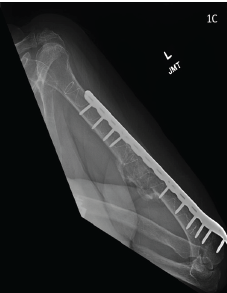

Use of the IlluminOss Implant for Treating a Pathologic Humeral Fracture in a Patient with Renal Cell Carcinoma Metastasis: A Case Report

Summer M Drees , Ajay Nair , Paul Swigart , Lucas Unver , David Yatsonsky , Kyle A Andrews

………………………………p.126-130